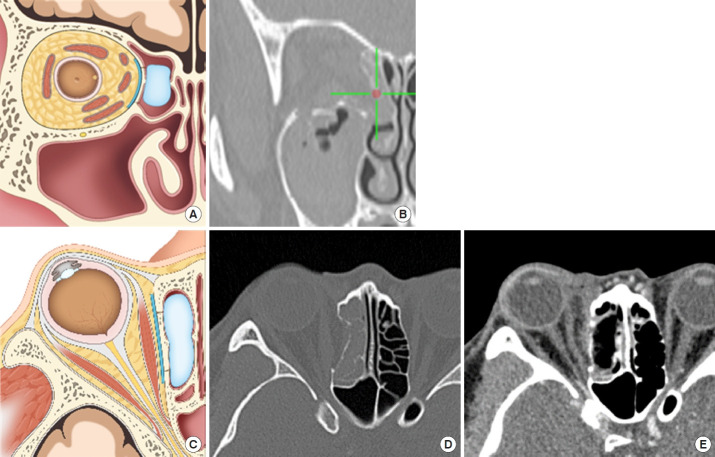

Craniofacial surgery requires comprehensive anatomical knowledge of the head and neck to ensure patient safety and surgical precision. Over recent decades, there have been significant advancements in imaging techniques and the development of real-time surgical navigation systems. Intraoperative navigation technology aligns surgical instruments with imaging-derived information on patient anatomy, enabling surgeons to closely follow preoperative plans. This system functions as a radiologic map, improving the accuracy of instrument placement and minimizing surgical complications. The introduction of first-generation navigation systems in the early 1990s revolutionized surgical procedures by enabling real-time tracking of instruments using preoperative imaging. Initially utilized in neurosurgery, intraoperative navigation has since become standard practice in otolaryngology, cranio-maxillofacial surgery, and orthopedics. Since the 2000s, second-generation navigation systems have been developed to meet the growing demand for precision across various surgical specialties. The adoption of these systems in craniofacial surgery has been slower, but their use is increasing, particularly in procedures such as foreign body removal, facial bone fracture reconstruction, tumor resection, and craniofacial reconstruction and implantation. In Korea, insurance coverage for navigation in craniofacial surgery began in 2021, and new medical technologies for orbital wall fracture treatment were approved in August 2022. These technologies have only recently become clinically available, but are expected to play an increasingly important role in craniofacial surgery. Intraoperative navigation enhances operative insight, improves target localization, and increases surgical safety. Although these systems have a steep learning curve and initially prolong surgery, efficiency improves with experience. Calibration issues, registration errors, and soft tissue deformation can introduce inaccuracies. Nonetheless, navigation technology is evolving, and the integration of intraoperative computed tomography data holds promise for further enhancements of surgical accuracy. This paper discusses the various types and applications of navigation employed in craniofacial surgery, highlighting their benefits and limitations.